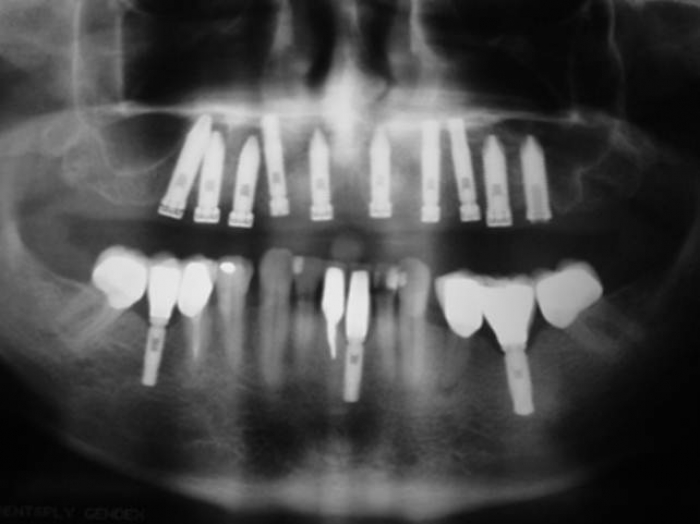

Raio X dos implantes

Raio X da prótese fixa em porcelana superior